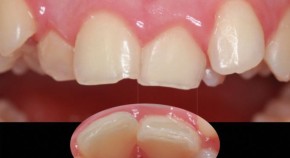

Bringing together a selection of articles from across the BDJ Portfolio, this Collection relates to the theory and practice of orthodontics. It features the BDJ Special Issue on the Orthodontic-Restorative Interface with contributions by leading national and international clinicians and researchers. Guest edited by Padhraig Fleming, it provides a contemporary, international perspective on adult orthodontics and combined orthodontic-restorative care.